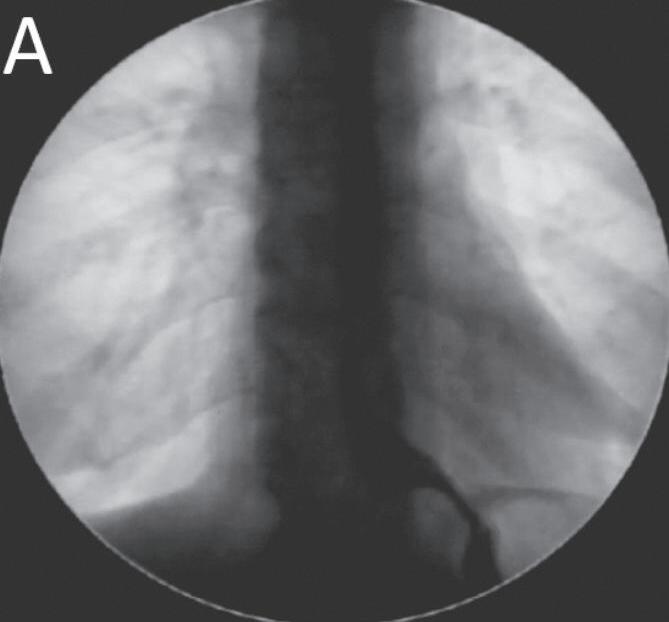

Figura 8.6 (A a C) (continuação) Manometria de alta resolução com IRP deitada de 18,9mmHg e sentada de 9,8mmHg e corpo com motilidade normal (C). Optou-se por conduta expectante

A terapia farmacológica com bloqueadores de canais de cálcio, nitratos, antidepressivos tricíclicos, inibidores de bomba de prótons (IBP), acotiamida e antiespasmódicos (hioscina) foi utilizada em alguns estudos de pacientes com OFJEG com resultados que variaram de 0% a 75% de sucesso.46-49 A injeção endoscópica de toxina botulínica

no EEI é uma opção terapêutica de baixo risco amplamente utilizada em casos de OFJEG primária (Figura 8.7).

As séries de casos descrevem bons resultados imediatos em até 100% de alívio sintomático, com resultados sustentados de até 67% em 6 meses e 64% após 2 anos de acompanhamento.32,33,35,46,47

Figura 8.7 (A e B) Paciente do sexo feminino, 45 anos de idade, disfagia baixa para sólidos e líquidos constante, náuseas, pirose e perda ponderal não quantificada há cerca de 15 anos. Endoscopia digestiva alta exibindo dois divertículos de esôfago médio e esofagomanometria convencional com esôfago em quebranozes. A esofagografia confirmou dois divertículos de esôfago médio (A) e manometria de alta resolução em esôfago em britadeira com obstrução funcional da junção esofagogástrica (JEG) (B). Submetida à injeção de toxina botulínica da JEG, ficou assintomática por 16 meses